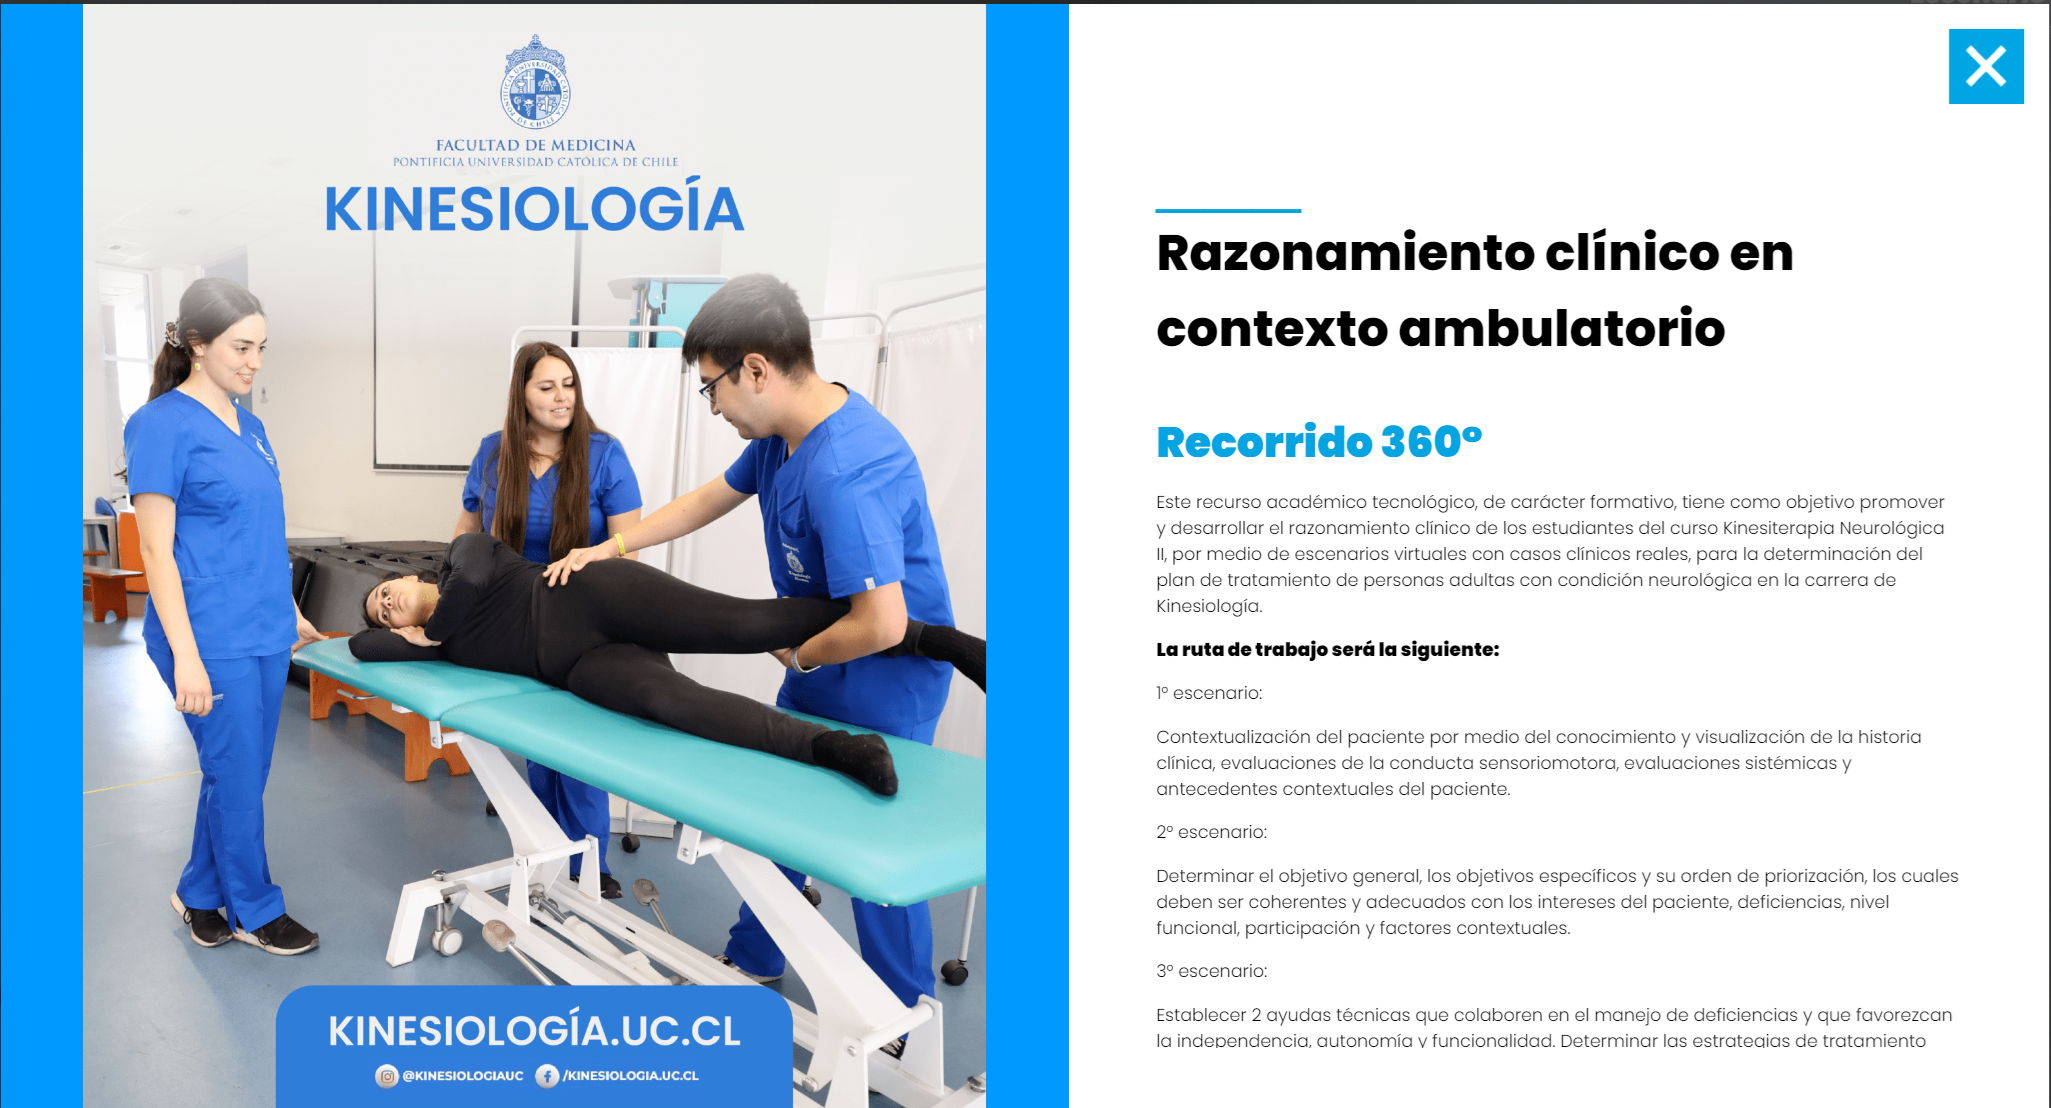

Innovaciones con tecnología

Con el propósito de difundir y masificar el uso de la tecnología en las prácticas docentes UC, en esta sección encontrarás distintas experiencias de aprendizaje, en donde el uso de herramientas tecnológicas ha influido en el éxito del proceso de enseñanza aprendizaje al interior del aula.